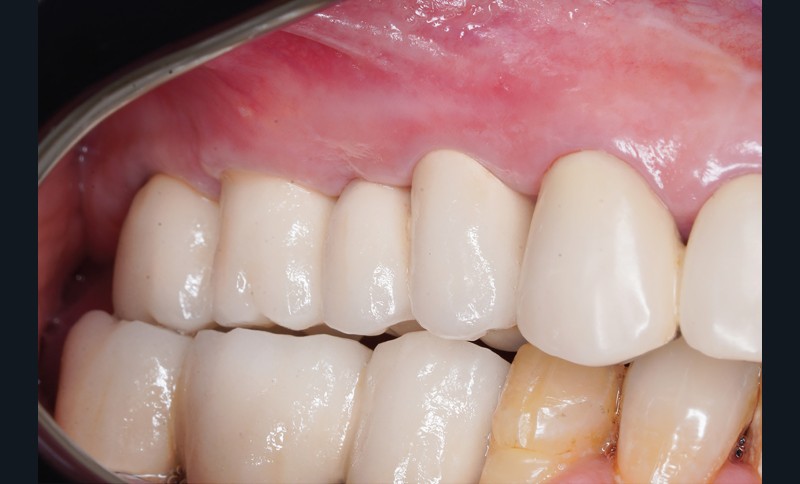

Une patiente de 52 ans en bonne santé, non fumeuse, a subi une augmentation osseuse et une greffe sinusale avec xénogreffe et membrane de collagène résorbable au niveau du maxillaire droit. Une chirurgie implantaire a été réalisée 9 mois plus tard et, après une période d’ostéointégration de six mois, les vis de cicatrisation ont été placées. Aucune des interventions chirurgicales n’a entraîné de complications. La patiente a conservé ces vis de cicatrisation pendant 6 semaines. Le praticien a ensuite pris une empreinte numérique et a opté pour des piliers personnalisés en titane et une restauration métallo-céramique scellée. Immédiatement après le scellement des restaurations, lors du même rendez-vous, le praticien a observé une suppuration provenant du sillon adjacent à l’implant 16 (fig. 1a).